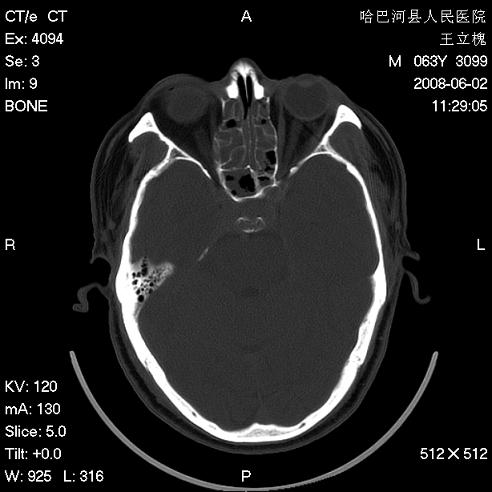

标题: CT13803:反复性鼻塞、流涕一年余 [打印本页]

标题: CT13803:反复性鼻塞、流涕一年余

全组副鼻窦炎 肌锥内高密度灶。建议进一步检察检查

1、全组副鼻窦炎。

2、左眼眶肌锥内病变,小血管瘤?建议增强。

1)全副鼻窦炎(左侧上颌窦黏膜下囊肿或息肉)。2)左眼眶肌锥内不规则小结节状软组织密度影;考虑为小血管瘤可能。建议行ct增强扫描检查。

全组副鼻窦炎,左侧肌锥内不规则形软组织肿块影,与眼外肌密度相当,左侧视神经受压,肿块与视神经及眼外肌分界清晰,眼外肌无增粗,眶壁无破坏,球后脂肪间隙不模糊,考虑良性改变,小血管瘤或神经源性肿瘤可能,建议增强扫描。

谢谢,增强扫描做了,眶内病灶与海绵窦同步明显强化,血管瘤